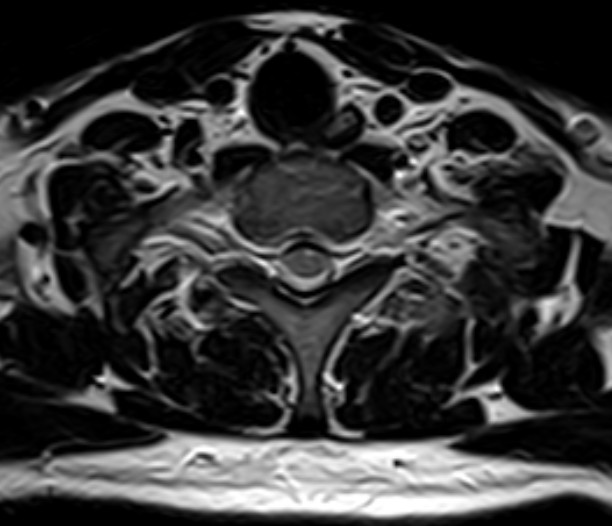

颈椎-T1